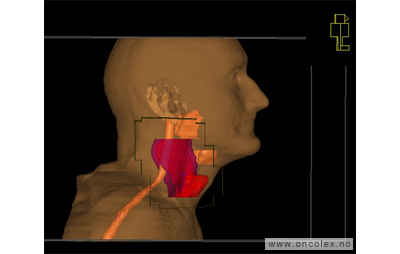

Bildeeksempler

• 70 Gy til svulsten (GTV)

• 46 Gy til eventuelt mikroskopisk sykdom (ITV)

• Samtidig gis boost 6 ganger i uken

• Alle felter skal behandles ved hver fraksjon.